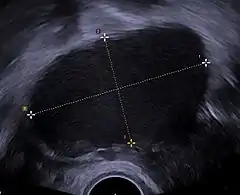

![]() Ecografía ginecológica en la que es visible un endometrioma ovárico de 67 x 40 mm. | ||